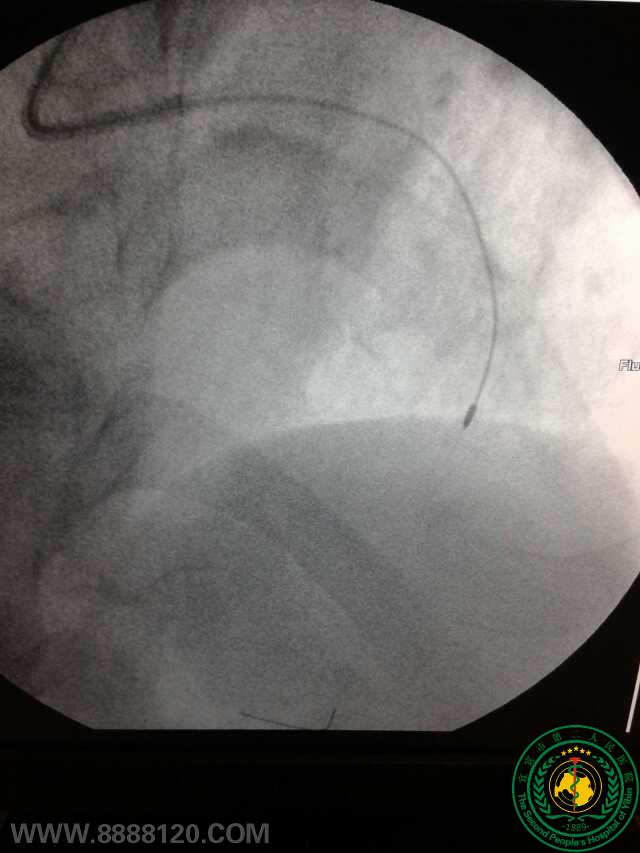

冠脉治疗新技术——宜宾首例冠脉旋磨术

宜宾市第二人民医院 图文